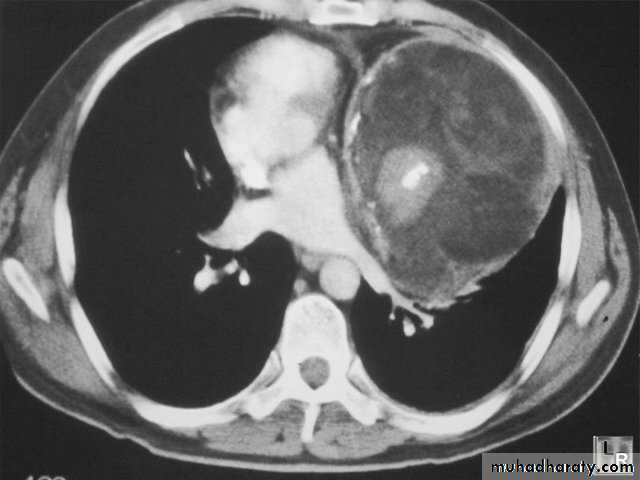

Pulmonary hydatid disease

Hydatid cyst

X-ray findings

Simple hydatid cyst